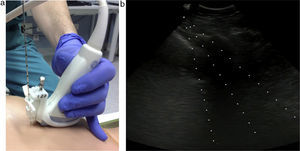

Intrathoracic lesions were initially evaluated using a 4MHz convex transducer. If the mass or nodule invaded the chest wall, a linear 7MHz transducer was also used (Fig. 1). Patients were placed supine, prone or lateral decubitus, according to the position which gave greater US access with the best safety profile.

Both techniques (core biopsy and FNA) were guided by real-time US imaging. A needle guide was attached to the transducer (Fig. 2) to ensure precision.